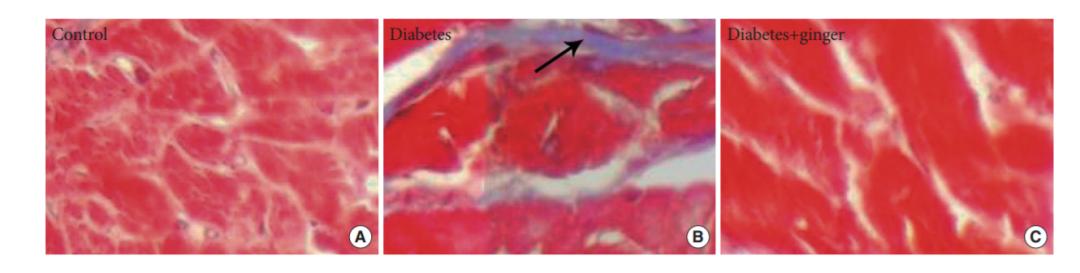

一些证据表明,生姜提取物可能有助于降低心血管疾病风险,5g或更多的剂量可以引起显著的、有益的抗血小板活性。同时,一项小型研究发现,生姜提取物有助于减少糖尿病大鼠心脏异常的发生。提示生姜可能被证明是治疗心血管疾病的一种安全补充剂。这可能得益于生姜提取物的抗氧化特性。

doi: 10.4093/dmj.2016.40.1.46